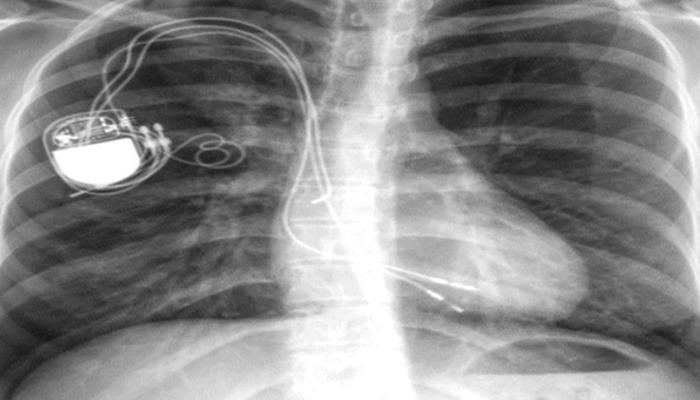

Kalbinde delik olarak dünyaya gelen Ayşenur Çalışkan'a 4 yaşında kalp pili takıldı. 9 ve 15 yaşlarında kalp pili jeneratörü değiştirilen Çalışkan, 24 yaşına geldiğinde göğüs kasılmaları, kolunda uyuşukluk ve kalp yetmezliği şikayetiyle Konya ve Ankara'daki hastanelere başvurdu.

Üçüncü kez kalp pili jeneratörü değişmesine rağmen hastalığı geçmeyen Çalışkan, Doç. Dr. Mevlüt Serdar Kuyumcu tarafından muayene edildi.

Çalışkan'ın tomografisini inceleyen Kuyumcu, 20 yıl önce takılan kalp pili kablosunun artık hastanın organlarına bağlandığını, kablonun birçok damara girip çıktığını, kablonun çekilmesi halinde hastanın hayatını kaybedeceğini fark ederek, çalışmalara odaklandı. kabloyu çıkarmadan hastayı tedavi etmek.

Kuyumcu, Kardiyolog Doç. operasyonda ona yardım eden kişi. Dr. Con Bayram Ali Uysal, hastanın karın boşluğundaki teli keserek, yaklaşık 3 saatte açık kalp ameliyatı yapmadan içerideki 20 santimetrelik onlarca metal teli dış tabakaya zarar vermeden çıkardı. Bu ameliyatın ardından Çalışkan'a yeni kalp pili sistemi (jeneratör ve lead) takıldı ve ertesi gün hastaneden taburcu edildi.